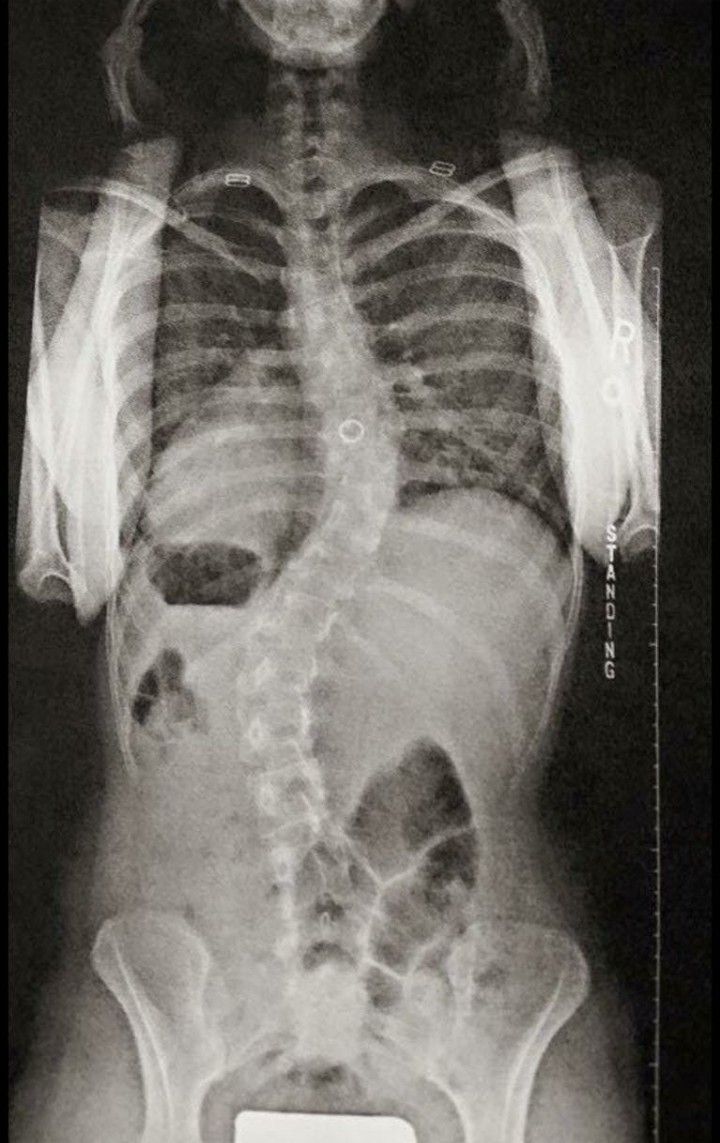

What is scoliosis?